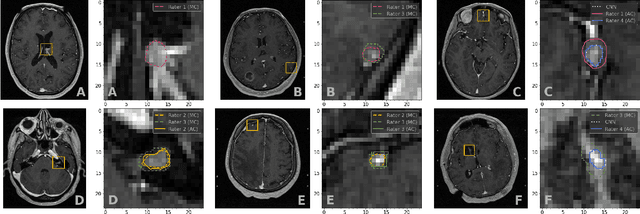

Abstract:We systematically evaluate a Deep Learning (DL) method in a 3D medical image segmentation task. Our segmentation method is integrated into the radiosurgery treatment process and directly impacts the clinical workflow. With our method, we address the relative drawbacks of manual segmentation: high inter-rater contouring variability and high time consumption of the contouring process. The main extension over the existing evaluations is the careful and detailed analysis that could be further generalized on other medical image segmentation tasks. Firstly, we analyze the changes in the inter-rater detection agreement. We show that the segmentation model reduces the ratio of detection disagreements from 0.162 to 0.085 (p < 0.05). Secondly, we show that the model improves the inter-rater contouring agreement from 0.845 to 0.871 surface Dice Score (p < 0.05). Thirdly, we show that the model accelerates the delineation process in between 1.6 and 2.0 times (p < 0.05). Finally, we design the setup of the clinical experiment to either exclude or estimate the evaluation biases, thus preserve the significance of the results. Besides the clinical evaluation, we also summarize the intuitions and practical ideas for building an efficient DL-based model for 3D medical image segmentation.